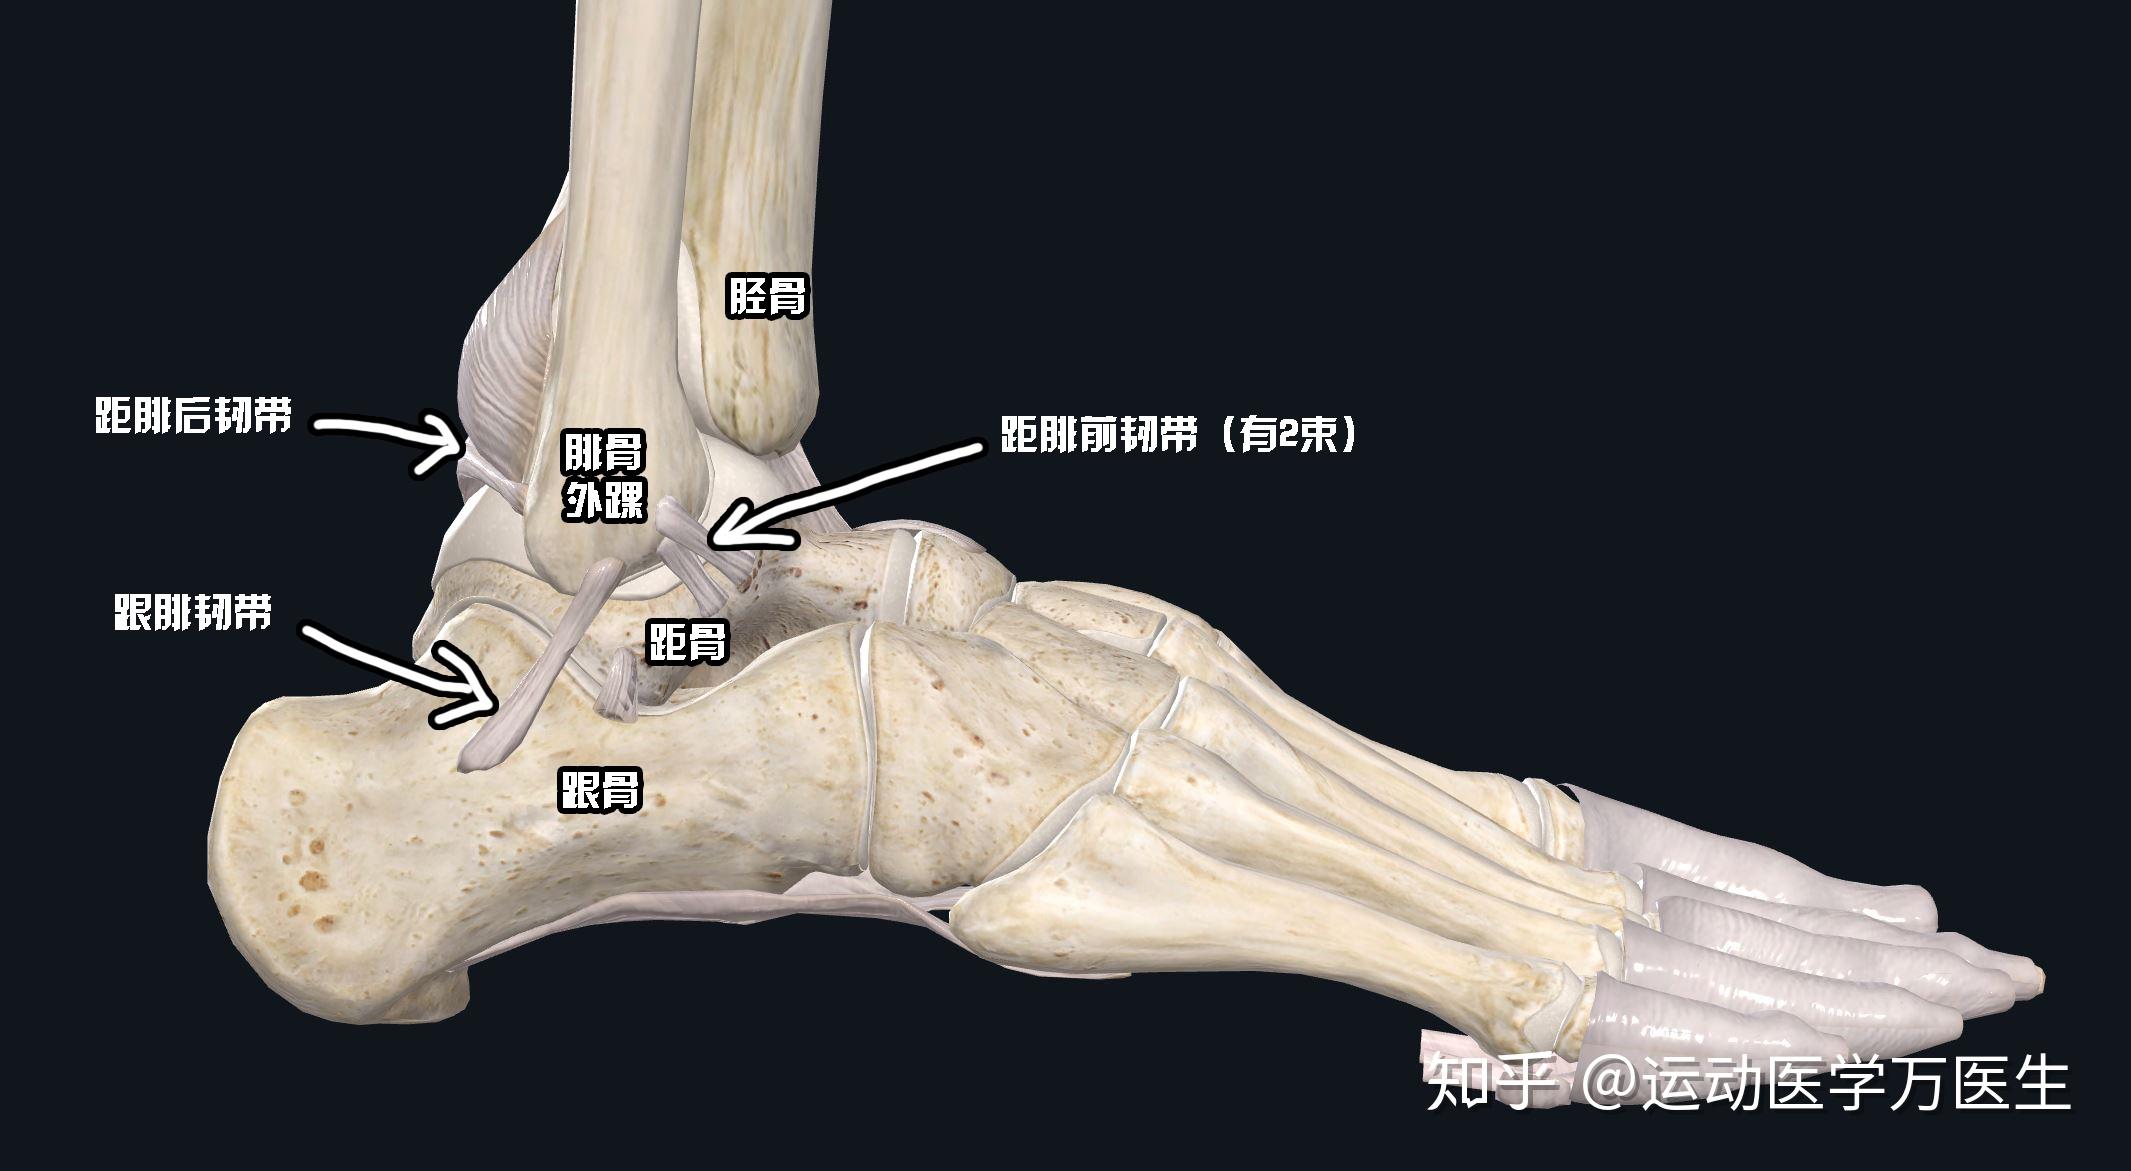

高清图解踝关节韧带解剖

图片尺寸660x495

喜欢的男生脚踝韧带撕裂他自己心情很不好我应该如何安慰

图片尺寸2131x1171